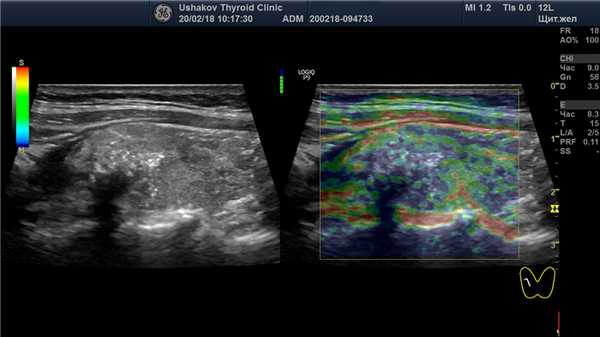

| Рисунок 4. Узел верхней (краниальной) части правой доли щитовидной железы (ограничен желтыми метками). Признаки рака узла: 1) неправильная форма, 2) неравномерный край узла, местами прерывистая граница, 3) значительно гипоэхогенная (темная) зона внутри узла, постепенно переходящая в остальную ткань, 4) микрокальцинаты. Класс по TI-RADS соответствует 4С. | Рисунок 5. Изменённый регионарный лимфатический узел. Отношение сторон меньше коэффициента 2 (округлый), внутри определяется значительное разрастание ткани (признак метастазирования). |

Рисунок 6. Этот же узел в режиме компрессионной эластографии. Значительно увеличена жесткость узловой ткани ― признак плотного расположения клеток в ткани узла и её разрушения с накоплением жидкости (свойственно злокачественности). Микрокальцинаты определяются в виде скоплений мелких белесых точек.